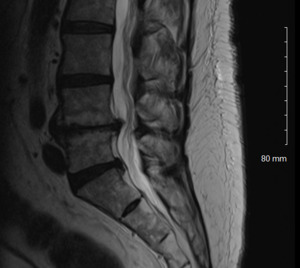

Physical examination revealed hypertonicity and tenderness in the lumbar paraspinal muscles and the left posterior hip region. He reported a pain level of 8/10 on the NPRS, reflecting both LBP and radicular symptoms. Additionally, a score of 32 out of 40 on the DVPRS indicated substantial pain-related functional impairment. A 2024 lumbar spine MRI demonstrated degenerative disc disease, arthropathy, severe left subarticular recess stenosis at L4-L5 with L5 nerve impingement, and a small left central disc extrusion at L5-S1 abutting the S1 nerve root (Figs. 1–4).

This case report documents an unexpected improvement in PLP during chiropractic treatment for LBP and radicular symptoms in a patient with a below-knee amputation. The temporary abolition of PLP reported at Visit 5, which was sustained for 2 weeks, suggests that automated lumbar long-axis distraction and myofascial release may influence the neuropathic pain pathways in amputee patients. Furthermore, lumbar distraction may reduce mechanical compression on the L5 nerve root, as seen on MRI (Figs. 1-4), potentially decreasing spinal cord hyperexcitability associated with PLP.15 Myofascial release, by addressing trigger points and muscle tension, may alter afferent input to the spinal cord, influencing pain processing.16 Chiropractic manipulation has been shown to modulate pain perception and widespread pressure sensitivity, likely through activation of descending inhibitory pathways. While these mechanisms may play a role in conditions involving central sensitization, their relevance to neuropathic pain such as PLP needs further investigation.17